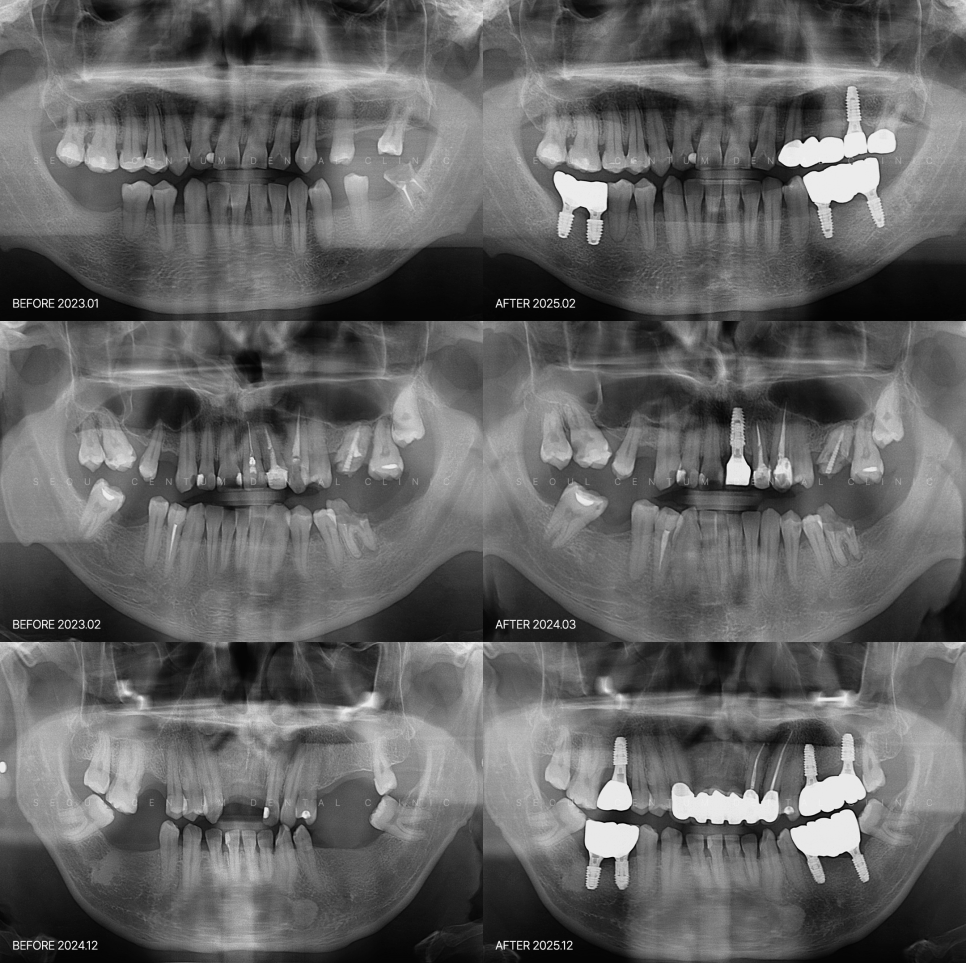

군 복무 중 치아 파절됐을 때는 어떻게 해야 할까요? 군대에서 훈련이나 여러 이유로 치아가 부러지는 상황이 발생할 수 있어요. 이 상황이 갑작스럽게 닥치면 당황스러울뿐더러 앞으로 치료를 어떻게 해야 하는지 막막하게 느껴지리라 생각합니다. 민간 치과를 통원하기에는 시간과 같은 장벽이 있으니까요. 군 병원에서라도 임플...